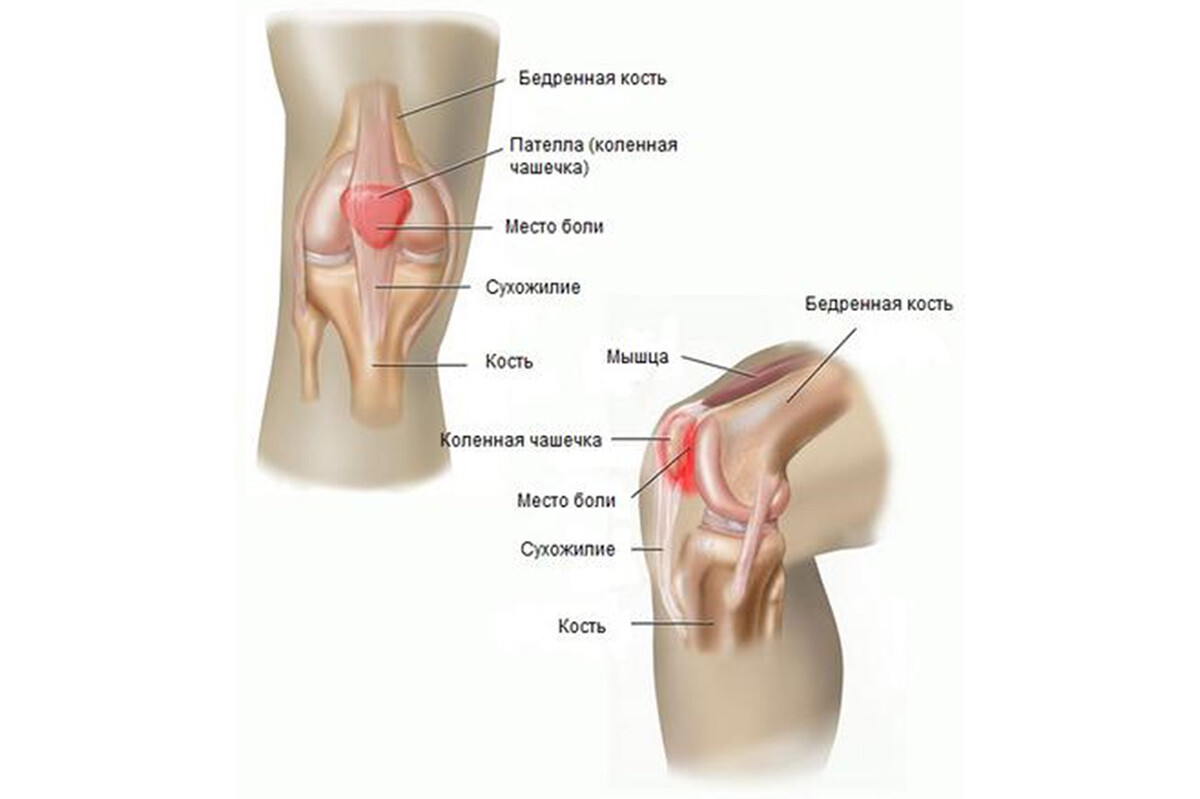

Заболевания и медицинские снимки: Жидкость в коленной чашечке